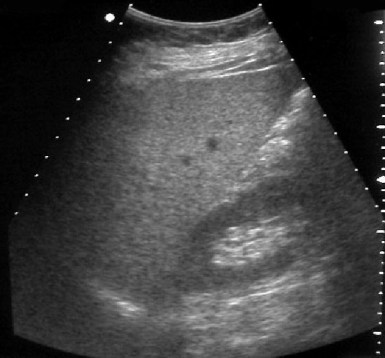

SIGNO DEL HÍGADO BRILLANTE

Signo visible en la ecografía, que consiste en el aumento de la ecogenicidad hepática de forma difusa, que se ve en la cirrosis y en la esteatosis hepática. En la imagen, el aumento de la ecogenicidad hepática se hace más evidente comparando con la ecogenicidad de la cortical renal.